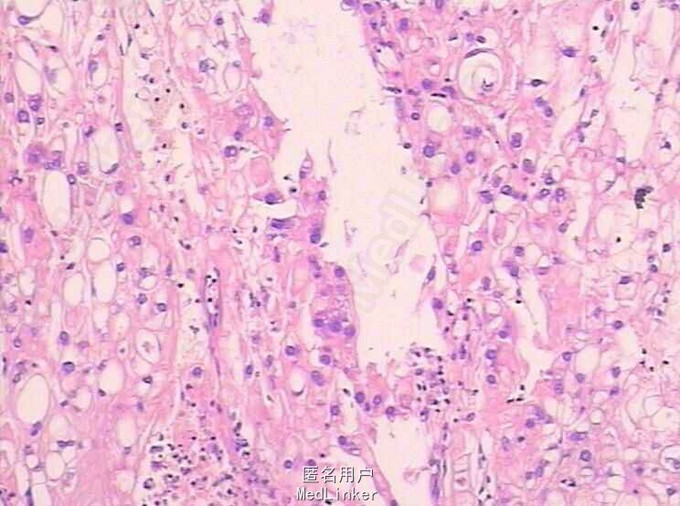

骶尾部疼痛 脊索瘤

诊断:(骶骨肿瘤)脊索瘤 在局麻下行骨活组织检查,术后病理示:(骶骨肿瘤)脊索瘤。后在全麻下行骶骨肿物切除术,术后给予抗感染,营养支持等对症治疗及相应的理疗及功能锻炼,患者症状明显缓解,切口愈合好。顺利出院。

随访:半年及此后每半年定期返院复查。 讨论:脊索瘤起源于胚胎残留的脊索组织。在胚胎期间,脊索上端分布于颅底的蝶骨和枕骨,脊索的下端分布于骶尾部的中央及中央旁等部位。